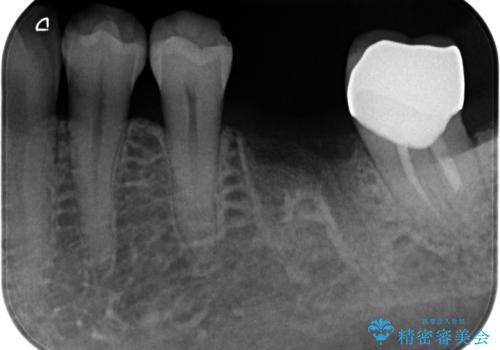

歯の破折 食べる喜びが蘇るインプラント治療

- 歯を破折により失ったため、義歯・ブリッジ・インプラント治療の3つの治療法を提案しました。

骨の量は十分あったため、比較的短期間で治療は終了しました。

安定した咬み合わせとなり、痛みもなく安心して噛めるようになりました。